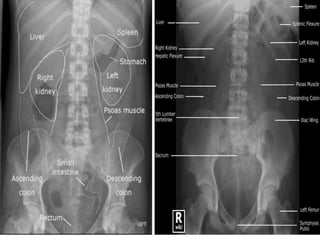

• scout film is taken including the kidneys,

ureters, bladder and urethral regions.

• Plain X-ray KUB /Scout film

Plain X-ray KUB -Useful in assessing

• Calculus

• Intestinal abnormalities

• Intestinal gas pattern

• Calcification

• Abdominal mass

• Foreign body